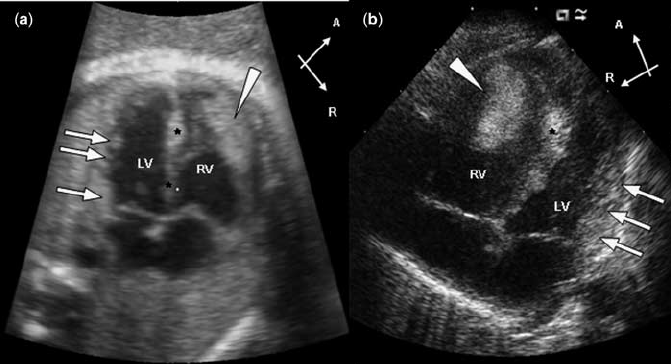

Echocardiogram treatment uses sound waves to produce images of your heart & see your heart beating and blood pump rate to identify heart disease. Looking for a doctor to diagnose your heart condition, such as shortness of breath or chest pain?